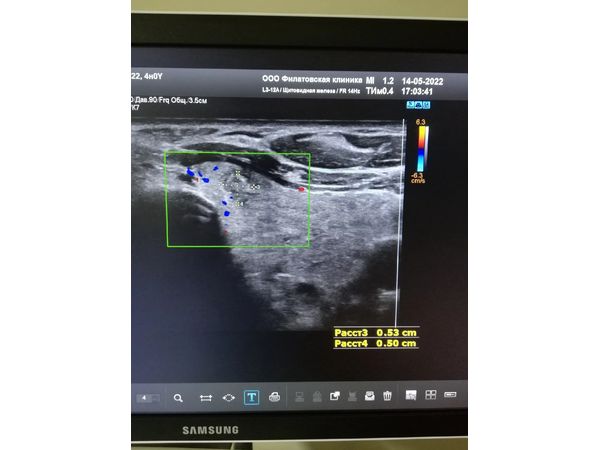

- TI-RADS 5 — округлое образование смешанной эхогенности размером 0,53×0,50 см с нечёткими, неровными контурами и множественными микрокальцинатами, без кровотока;